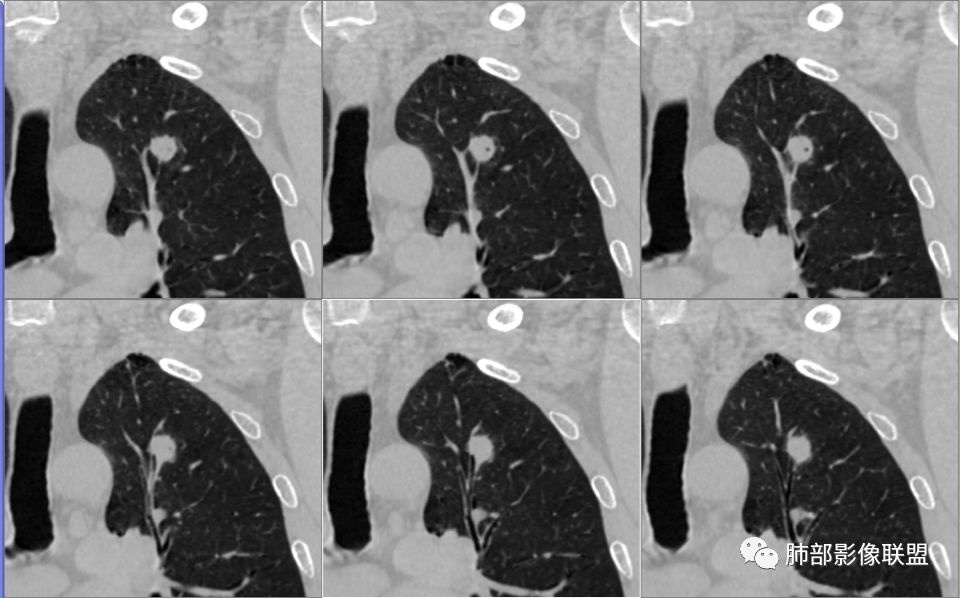

南大分析病例1

南边:

老年男性,因为头部症状来诊,也就是说肺部没症状

胸膜下结节,边界清楚、光滑,边缘稍凹陷,有胸膜牵拉

支气管在门口堵了

一般这类结节,边缘光滑

似有浅分叶

门口支气管堵塞——提示与支气管相关,不支持良性肿瘤

炎性?恶性?

符合炎性的地方:

实性,边缘凹陷,强化均匀

让我们不踏实的地方:

似乎有脐凹征

除了胸膜牵拉,还有短毛刺?血管纠集

支气管在门口堵塞

综合起来看,恶性不能排除。建议穿刺活检,一定要认清楚:我们影像有局限性。

应当说两例患者影像学表现都具有比较明显恶性征象,中老年男性患者,均都没有呼吸系统临床症状。

病例1为胸膜下实性小结节,血管脐凹样出入,可见支气管阻塞。病灶膨隆,部分边缘平直,周围晕征不明显,未见分叶,但可见毛刺及胸膜牵拉,增强后明显强化,老年男性,怀疑新生物尤其是腺癌是有理由的。